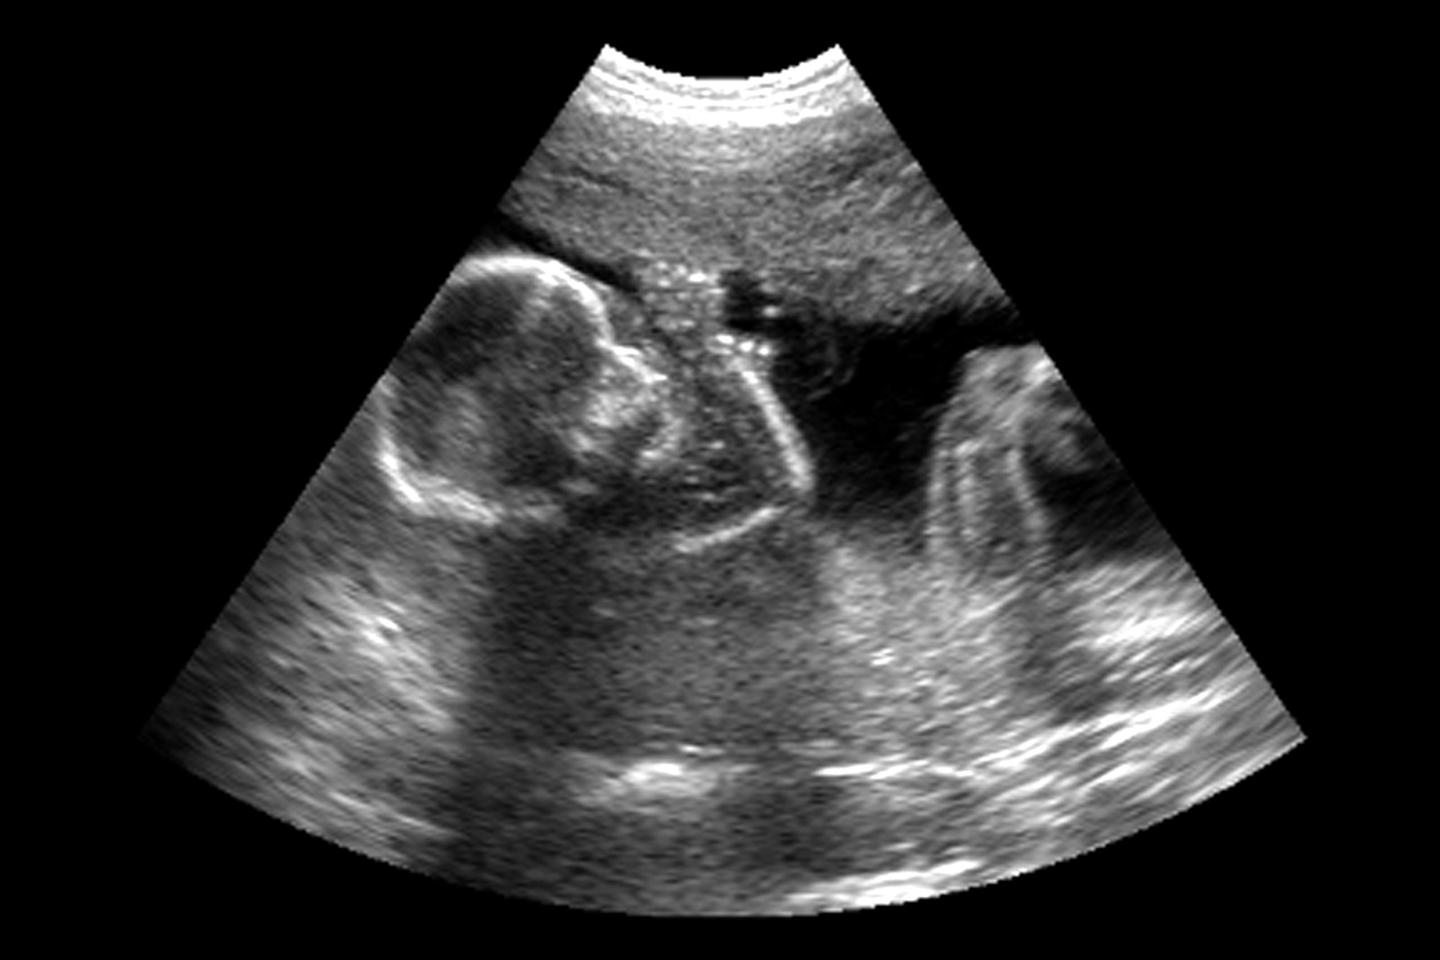

J’ai donc travaillé sur la coordination bimanuelle, sur la façon dont une main joue un rôle de support quand l’autre, généralement la droite, est plus active. J’ai fini par m’intéresser à la latéralité tout court. La stratégie à l’époque était d’observer l’enfant après la naissance, mais si on voulait remonter à l’origine, il fallait pouvoir l’étudier in utero.